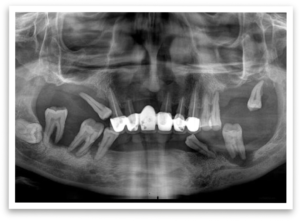

The day of the procedure arrived. Our team strategically placed four implants each in Mr. B’s upper and lower jaw (maxilla and mandible).  The immediate denture was then securely fixed onto the implants, immediately providing him with a functional and aesthetically pleasing smile.